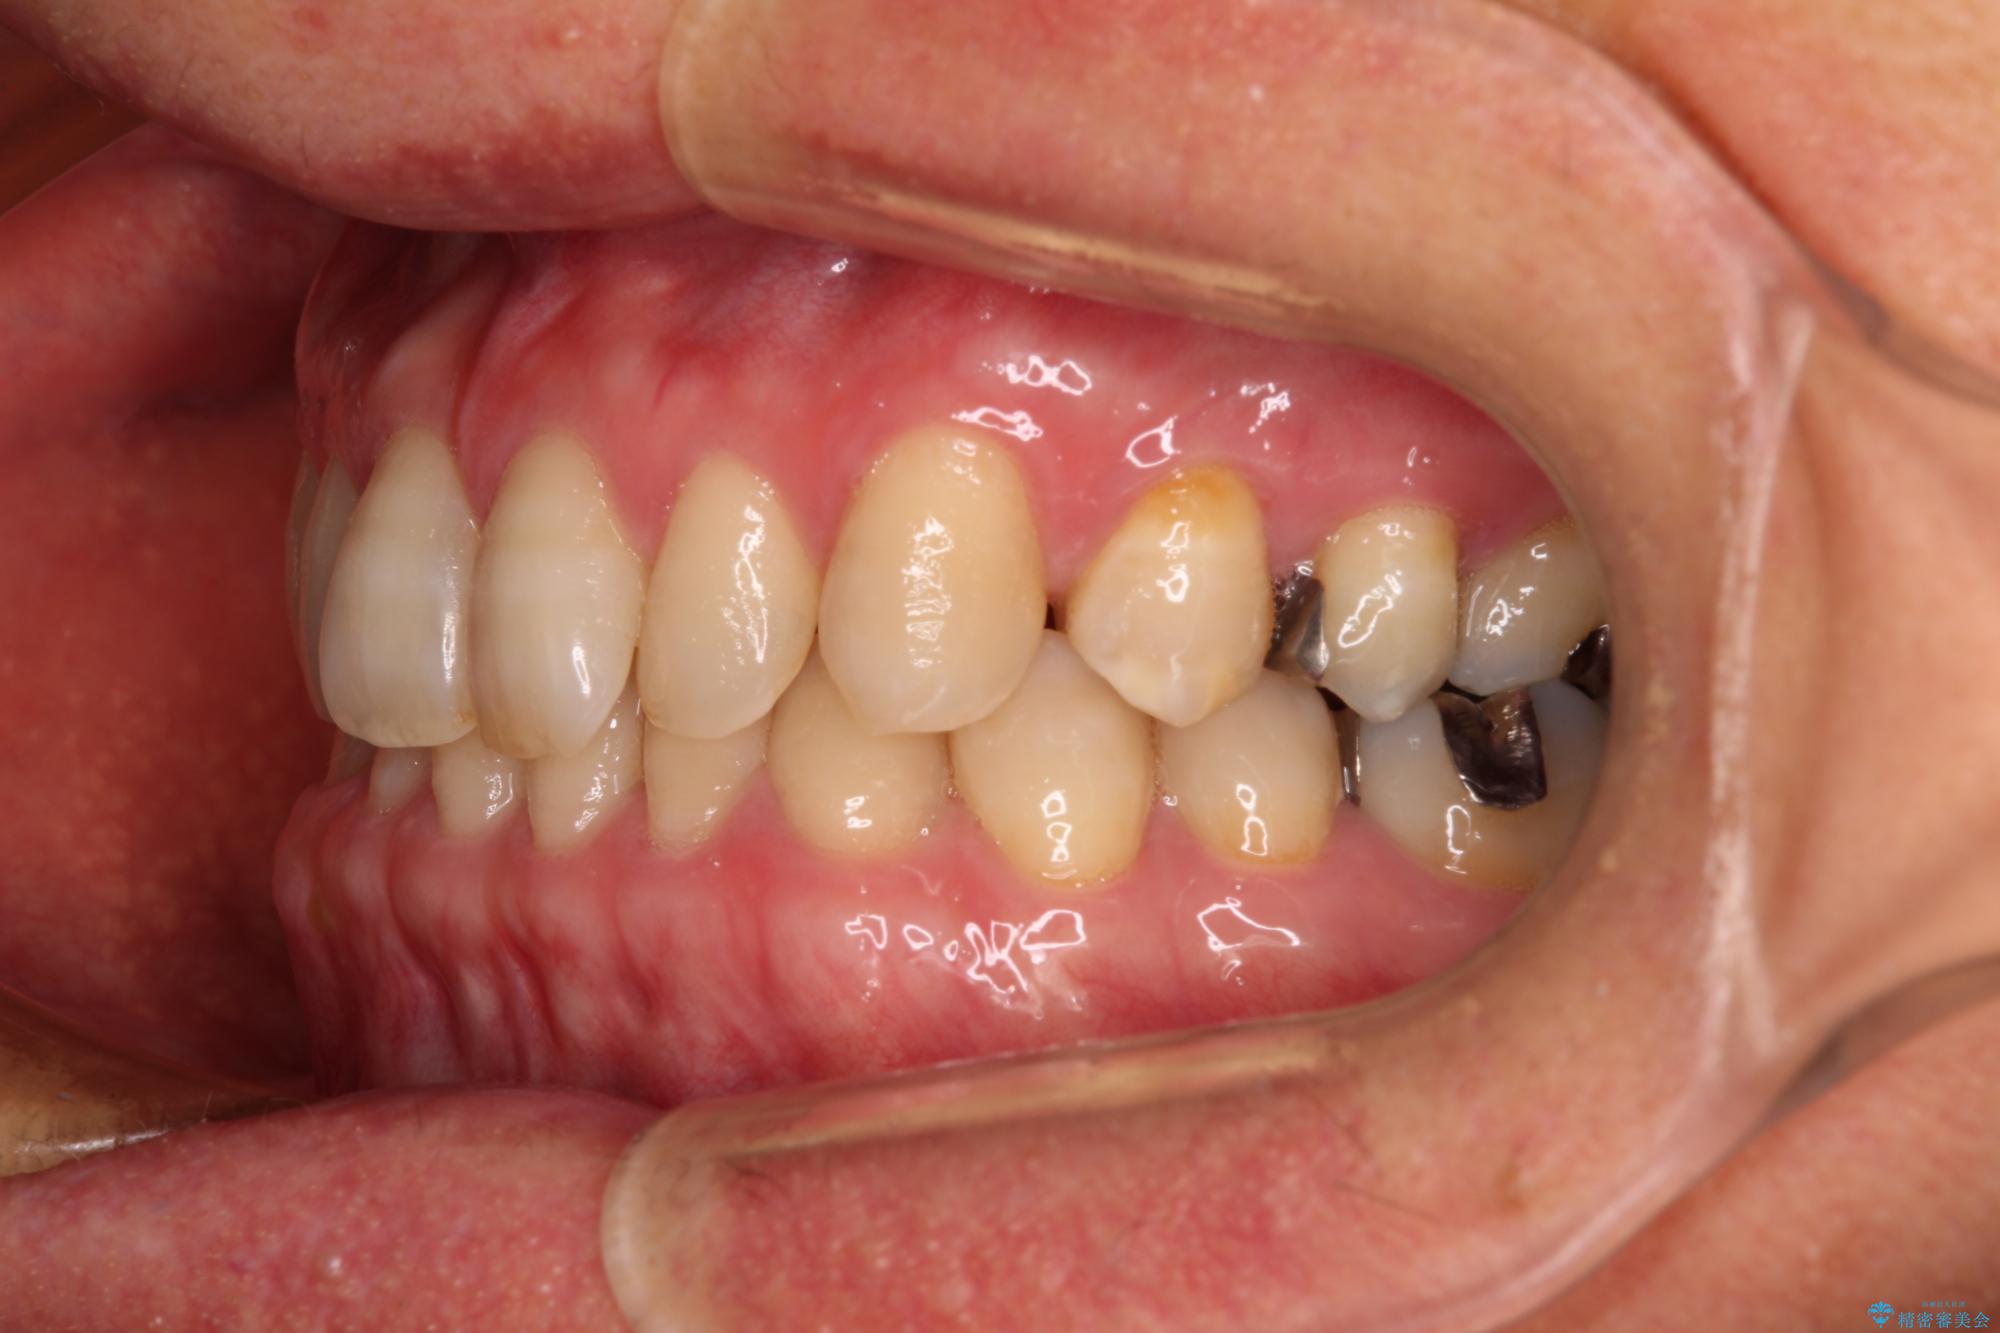

- 前歯のデコボコと隙間の空いた歯列を気にして来院された患者様です。

下顎前歯が隠れるほどのディープバイトにより、強い咬合力と突き上げで上顎歯列に隙間が空いている状態でした。

手前に傾斜している奥歯をワイヤー装置で立ち上がらせ、咬み合わせの高さを挙上することで突き上げを解消し、空隙歯列を改善していくこととしました。

ディープバイトが改善され、睡眠時の食いしばりも緩和され、顎への負担が軽減されました。